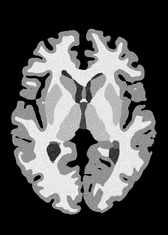

4.2 Registration to a 100 micron ex-vivo brain MRI volume

To showcase the efficacy of our method on real large scale images, we register a 250 in-vivo MRI image (Lüsebrink et al., 2017) to a 100 ex-vivo FLASH human brain volume (Edlow et al., 2019). This represents an inverse problem with more than 11.2B optimizable parameters (compared to 20M for clinical datasets), or 44.8GB of GPU memory. The entire problem does not fit on most GPUs, necessitating distributed multimodal registration. We optimize a composite transform - affine followed by a diffeomorphic mapping; details can be found in Section E.1. Multimodal deformable registration took 58 seconds on 8 NVIDIA A6000 GPUs, which is unprecedented at this resolution. Fig. 6 shows qualitative results, highlighting the ability to register highly detailed structures such as cerebellar white matter; these structures are not visible at macroscopic scales. The resultant advantages of performing registration at this scale can allow researchers to characterize the neuroanatomy at microscopic resolutions and allow morphometric analysis of cortical layers and subcortical nuclei among other structures.